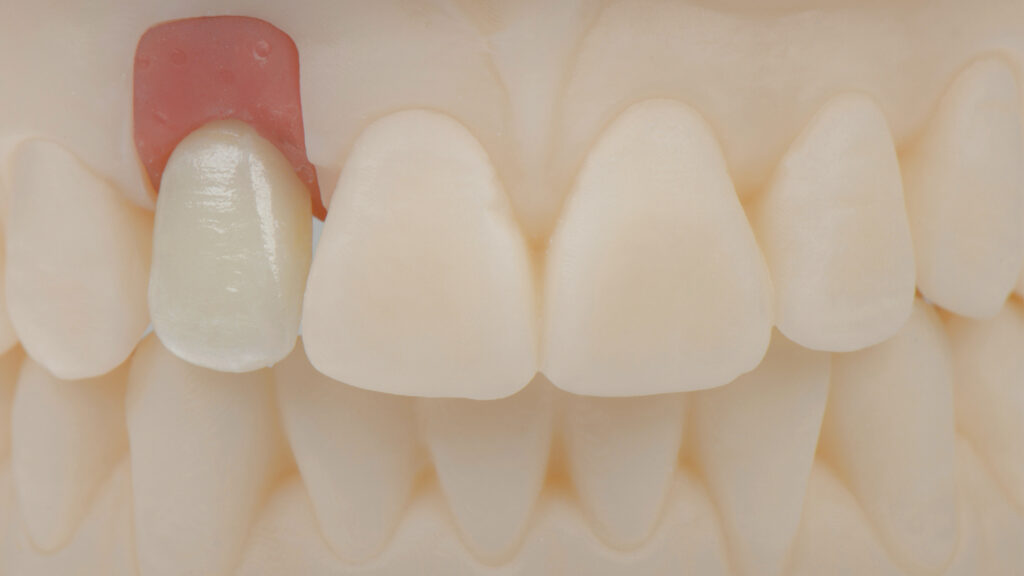

Herstellung des Eierschalen-Provisorium (TempShell)

Die STL-Datei der provisorischen Implantatkrone wird automatisch erzeugt, ein TempShell (Eierschalenprovisorium) konstruiert und die STL-Datei exportiert. TempShell ist ein verschraubtes Provisorium, das noch am Tag des chirurgischen Eingriffs eingesetzt werden kann. Es wird für jeden Patienten digital erstellt und kann mit DTX Studio Suite einfach an die Implantatposition angepasst werden. Anhand des Datensatzes wird CAD/CAM-gestützt das Provisorium aus PMMA gefräst (Abb. 11). Das gefräste Provisorium (TempShell) hat zwei Flügel. Diese sorgen für die richtige Position und Stabilität im Mund (Abb. 12 und 13). Durch On-Screen-Design-Verfahren passt das Provisorium perfekt auf das gedruckte Modell und in den vorgeschliffenen Gingivaverlauf (Abb. 14).